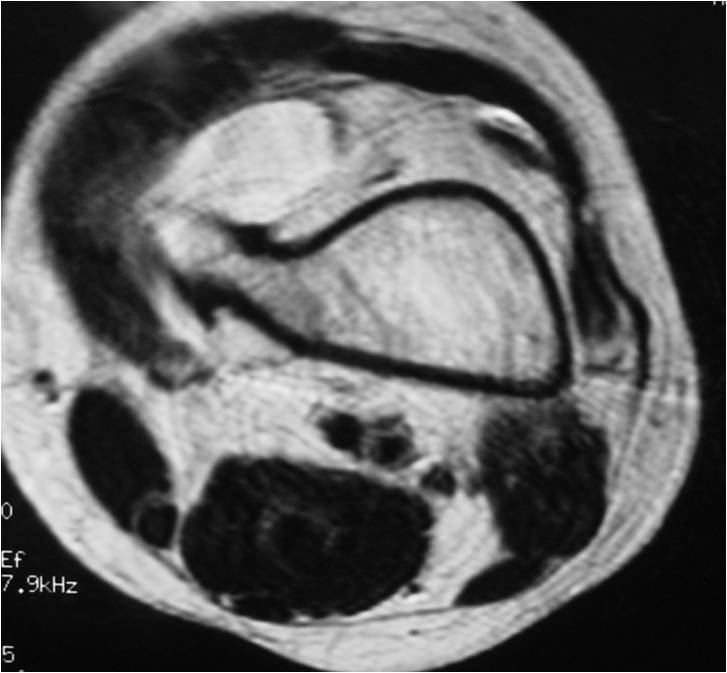

- Best test for evaluating thickness of cap and surrounding bursa

- Intermediate T1W Images

- High Intensity T2W Images because of fluid content

- Bursa may exist external to cartilage cap (seen on MRI)